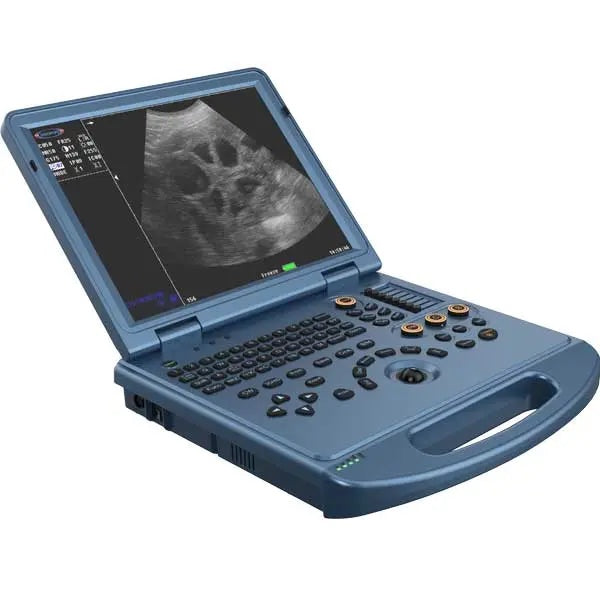

ECO-17Vet High end equine Ultrasound with Rectal Probe 4-12MHZ

High quality laptop Ultrasound

ECO17Vet High end Equine ultrasound with Top image quality.

1. Highly integrated hardware module with a lightweight body taking into account high-quality images, which provides great convenience for diagnosis.

4. Lightweight body and high quality images, built-in high-capacity lithium battery, support real-time three-dimensional imaging function.

Monitor: ≥ 15 inches